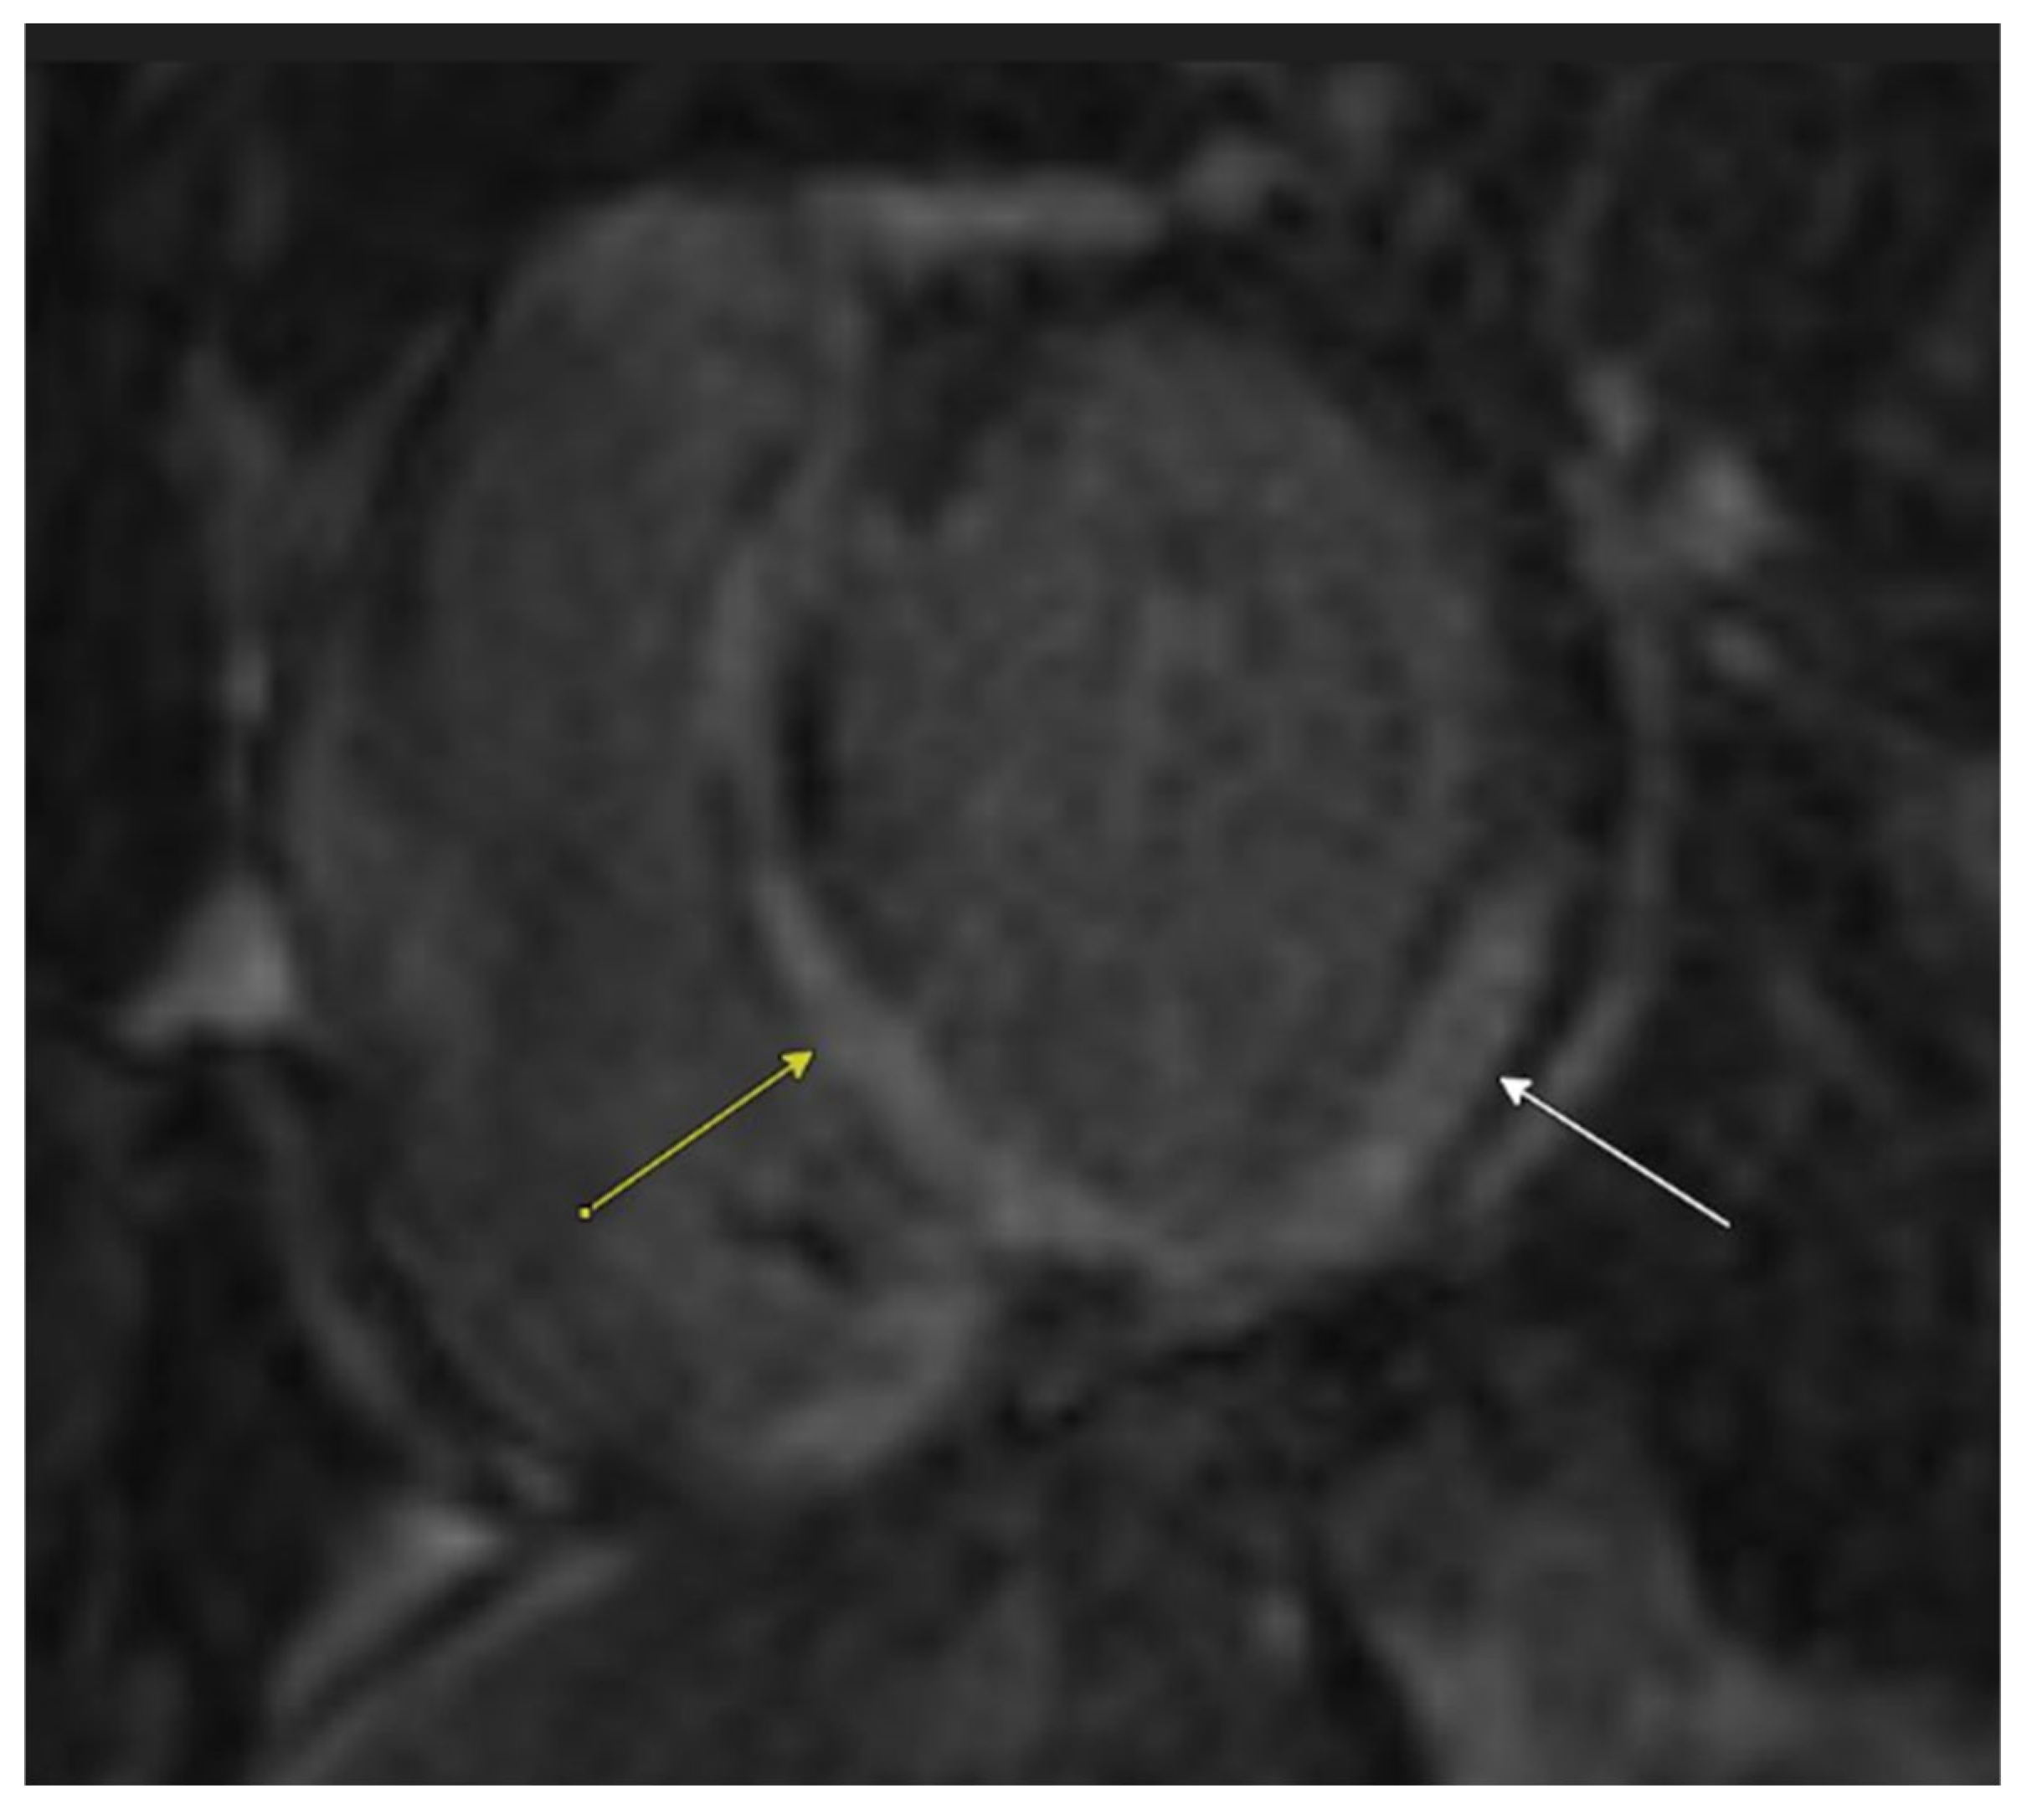

Cardiac MRI confirmed biventricular dysfunction, with left ventricular ejection fraction of 12%, right ventricular ejection fraction of 18%, basal septal akinesis/dyskinesis, and extensive abnormal late gadolinium enhancement, further supporting the suspicion of CS (Figure 3 and Figure 4). While there were no clinical signs of non-sarcoid inflammatory cardiomyopathy, a Positron Emission Tomography (PET) scan showed a very large area of diffuse myocardial FDG uptake with associated perfusion abnormalities, as described in the bull’s eye diagram, further supporting the diagnosis of CS (Figure 5). Except for cardiac abnormalities, a full-body CT PET was negative. CT coronary angiography revealed patent coronary arteries, while CT pulmonary angiography showed chronic nonocclusive segmental acute pulmonary embolus in the posterior right lower lobe without right heart strain. Ultrasonography Doppler of the lower extremities identified subacute nonocclusive superficial venous thrombosis involving the small saphenous vein, consistent with the patient’s history of KT syndrome.

Figure 4.

Cardiac MRI with late post-gadolinium-enhanced inversion recovery imaging in a short axis view at the base demonstrates extensive abnormal left ventricular myocardial late enhancement in a mid-wall and epicardial predominant distribution, particularly involving the basal inferior wall, septum (yellow arrow), and inferolateral wall (white arrow).